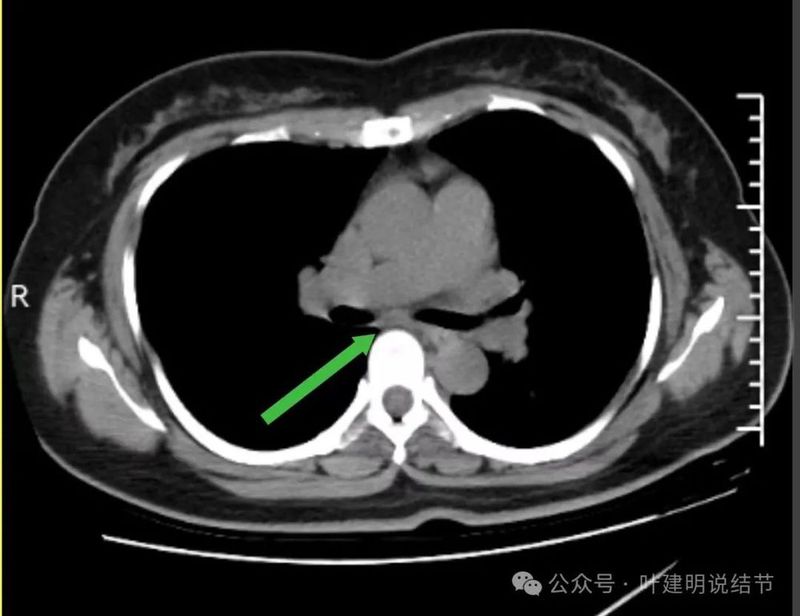

当时隆突下淋巴结小,说不上明显异常。

上腔静脉旁淋巴结也不大。